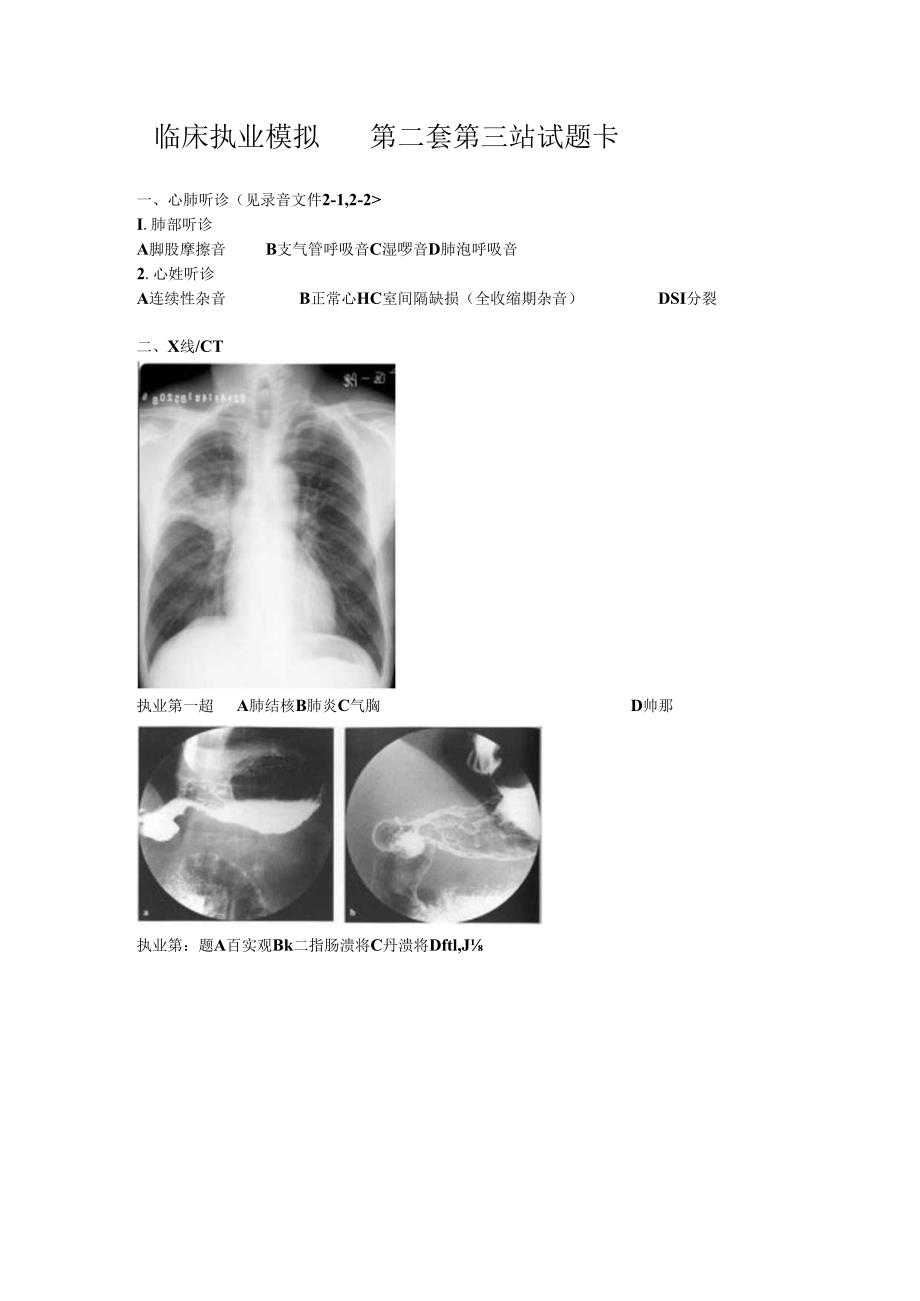

临床执业模拟第二套第三站试题卡一、心肺听诊(见录音文件2-1,2-2I.肺部听诊A脚股摩擦音B支气管呼吸音C湿啰音D肺泡呼吸音2.心姓听诊A连续性杂音B正常心HC室间隔缺损(全收缩期杂音)DSI分裂二、X线/CT执业第一超A肺结核B肺炎C气胸D帅那执业第:题A百实观Bk二指肠溃将C丹溃将Dftl,J执业第三题A肺娓B肺结核C肺炎D正常胸部CT三、心电图执业笫一座A前间壁心肌视死B广泛前壁心肌梗死C心肌缺血D心动过缓,.-1.8iW成JliiSHsSM三SS三一1霜匕叫一一.t-i-gCI1.执业第二题A广泛前鸵心肌便死B前间壁心肌梗死C完全性右束支传导阻滞D完全性左束支传导阻滞四、医卷医风患者,女,25岁,便血半月来医院就诊,你作为见医生,在给患者体检时,第项是对的?A涉及敏感部位的检查,应有女护士陪同B体检是医生的职业行为,不用考虑其他C男医生不得为女患者进行必要的核锂D为俣生特殊情况卜才能为女患者检杳